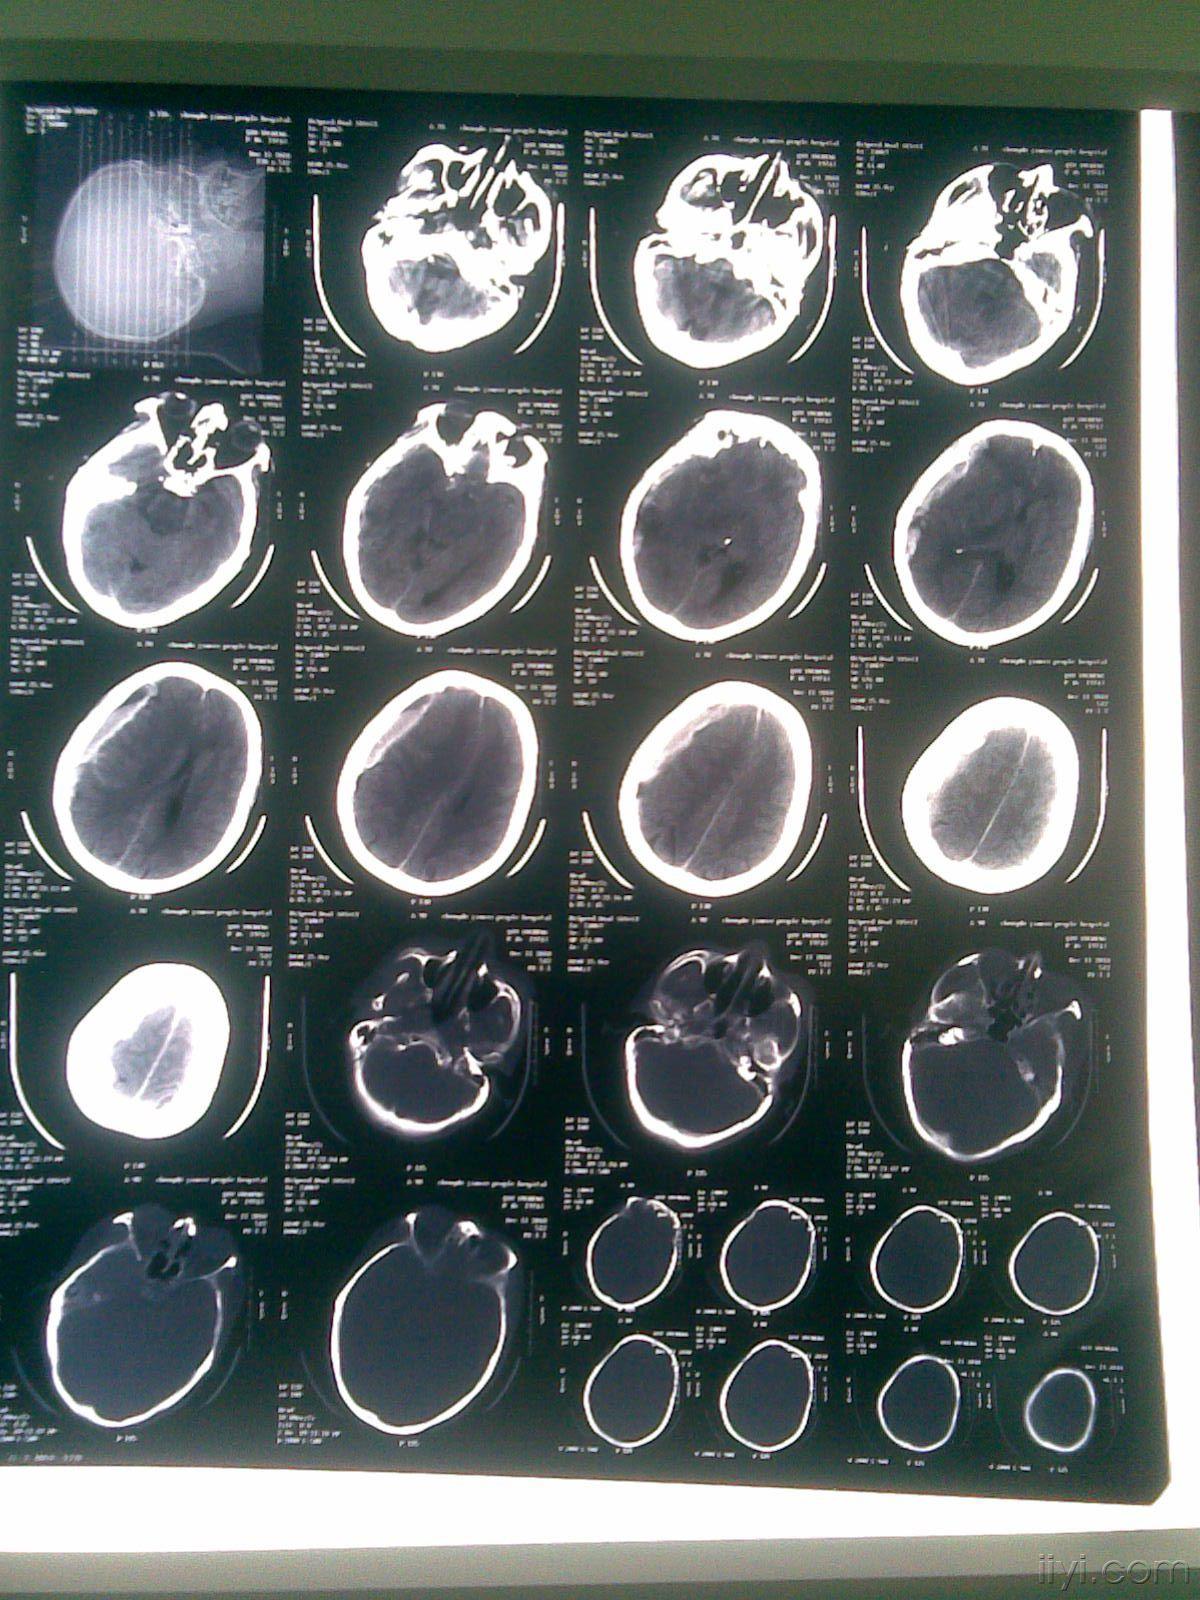

脑疝病人救治.男,21岁,车祸导致昏迷 1小时入院,急诊ct - 抖音

图片尺寸1439x1920

车祸伤脑疝

图片尺寸1200x1600